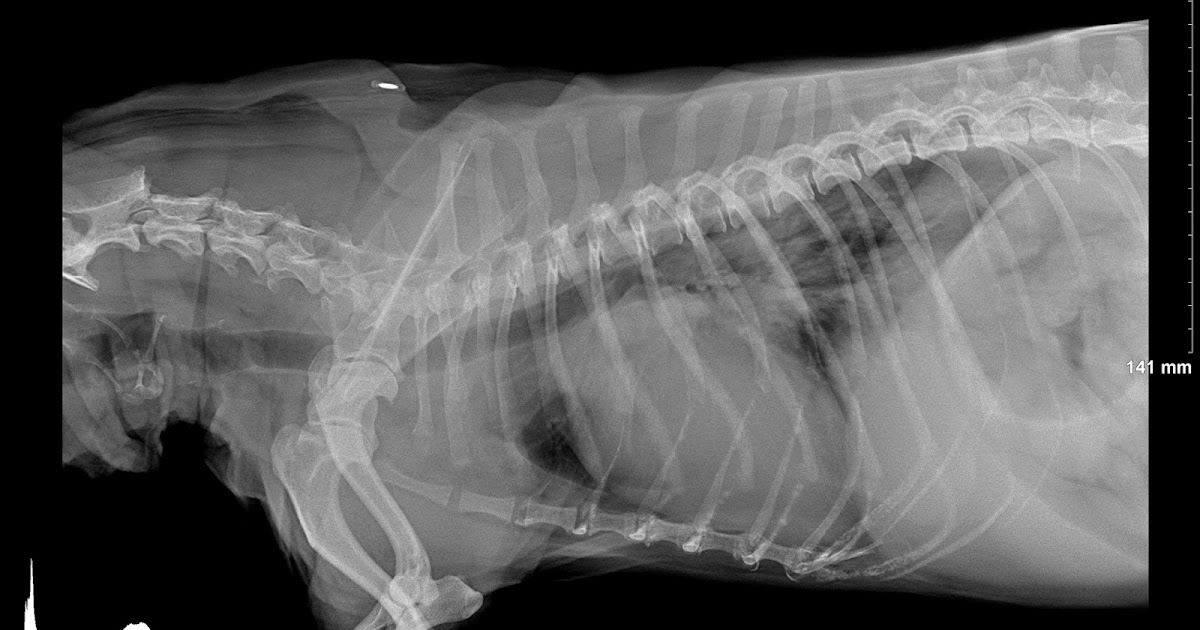

Veterinary, Photography and Travel Stories for vet students and pet Shih Tzu Kennel Cough Kennel cough, also known as canine infectious tracheobronchitis, is a highly contagious respiratory infection that causes a. The classic symptom of kennel cough is a persistent, forceful cough. Kennel cough is common, and there are ways to treat it at home. Kennel cough is an infectious bronchitis of dogs characterized by a harsh, hacking cough that most people describe as. Shih Tzu Kennel Cough.